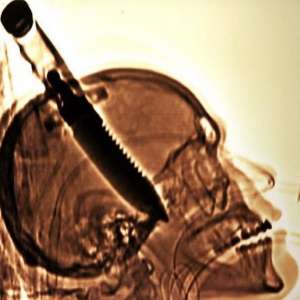

В 1998 году Майкла Хилла ударили в голову 8-дюймовым ножом, и он попал прямо в мозг. Этот случай был занесен в Книгу рекордов Гиннеса как «крупнейший объект, извлеченный из человеческого черепа».

Хотя Майкл выжил и не заразился инфекцией, удар ножом парализовал его левую руку и повредил память.